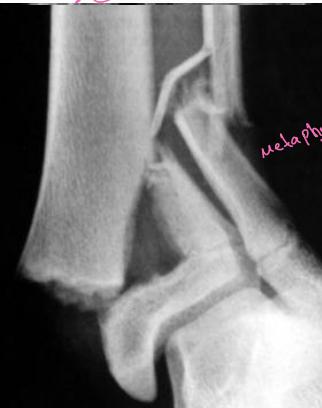

Compressed Type (Type V)

- Doesn’t appear on x-ray at first

- Cast & healed but prognosis is unpredictable

- Usually causes affection of growth arrest

- Diagnosed in retrospect!